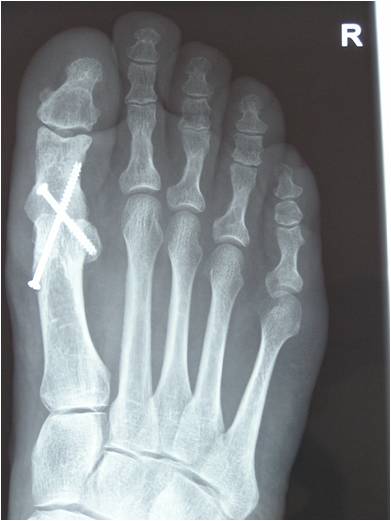

If the disease is more advanced either a joint fusion (arthrodesis)(Fig 3) or a joint replacement (Fig 4) can be considered. The former leaves the joint stiff but pain free, whereas the latter involves implanting an artificial joint which allows some joint movements whilst reducing or eliminating pain.

Arthrodesis or the fusion of the big toe joint is also done as day surgery. This operation involves the removal of the joint surfaces of the affected big toe followed by fixing the bones with metal work and requires 6 weeks protection in a weight-bearing heel-wedge postop shoe or occasionally a cast.